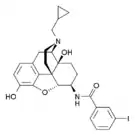

Structures of Morphine family

| Morphine family | ||||

|---|---|---|---|---|

14-Hydroxymorphine 14-Hydroxymorphine |

2,4-Dinitrophenylmorphine 2,4-Dinitrophenylmorphine |

6-Methyldihydromorphine 6-Methyldihydromorphine |

6-Methylenedihydrodesoxymorphine 6-Methylenedihydrodesoxymorphine |

6-Acetyldihydromorphine hydrochloride 6-Acetyldihydromorphine hydrochloride |

Azidomorphine Azidomorphine |

Chlornaltrexamine Chlornaltrexamine |

Chloroxymorphamine Chloroxymorphamine |

Desomorphine Desomorphine (Dihydrodesoxymorphine) |

Dihydromorphine Dihydromorphine |

Ethyldihydromorphine Ethyldihydromorphine |

Hydromorphinol Hydromorphinol |

Methyldesorphine Methyldesorphine |

N-Phenethylnormorphine N-Phenethylnormorphine |

6-nicotinoyldihydromorphine 6-nicotinoyldihydromorphine |

RAM-378 RAM-378 | ||||